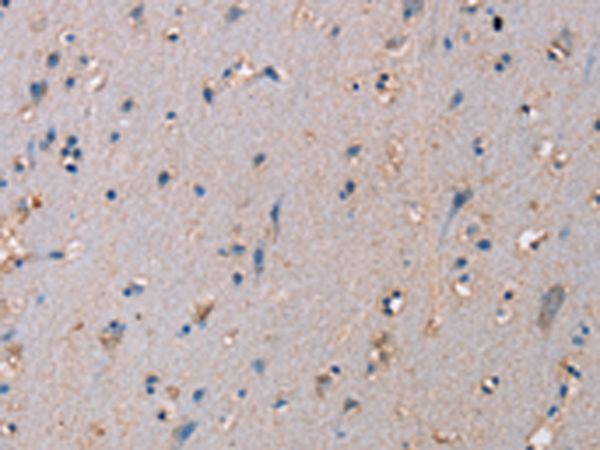

分类: 科研抗体货号: P04601别名: HUPF1; NORF1; RENT1; smg-2; pNORF1应用: WB,IHC反应种属: Human, Mouse